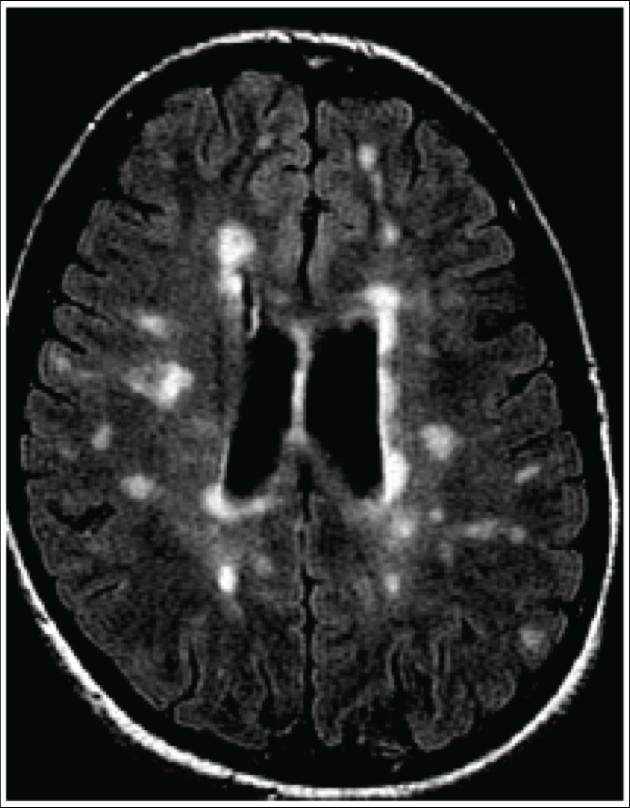

MRI shows 'brain scars' in military personnel with blastrelated concussion What Are Scars On The Brain Brain lesions can be caused by injury, infection, exposure to certain chemicals, problems with the immune system, and more. This is known as gliosis. The size, location, and appearance of the scar may vary depending on the area of the brain affected and the type of. Brain scar tissue, also known as cerebral scarring or gliosis, is a type of. What Are Scars On The Brain.

MRI shows 'brain scars' in military personnel with blastrelated What Are Scars On The Brain The size, location, and appearance of the scar may vary depending on the area of the brain affected and the type of. Brain lesions can be caused by injury, infection, exposure to certain chemicals, problems with the immune system, and more. This is known as gliosis. Brain aneurysm surgery may cause a scar at the incision site. A process that. What Are Scars On The Brain.

MRI Shows 'Brain Scars' In Mil [IMAGE] EurekAlert! Science News Releases What Are Scars On The Brain Brain lesions can be caused by injury, infection, exposure to certain chemicals, problems with the immune system, and more. This is known as gliosis. Controlled scar formation in the brain. Brain scar tissue, also known as cerebral scarring or gliosis, is a type of dense, fibrous tissue that forms in response to injury. The size, location, and appearance of the. What Are Scars On The Brain.